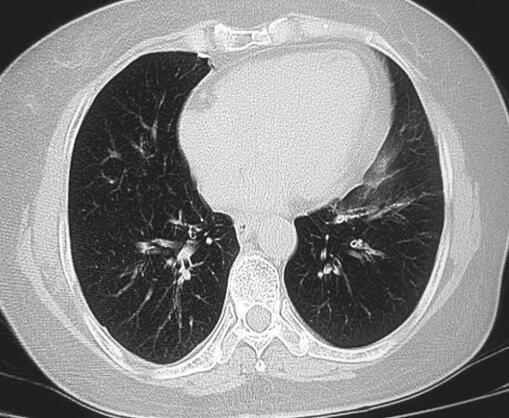

结合药敏试验,给予哌拉西林舒巴坦抗感染,同时给予祛痰止咳、降低气道高敏性治疗,10天后患者咳嗽、咳痰症状好转,但仍有阵发性咳嗽及气促,双肺呼吸音偏低,未闻及干、湿性啰音。给予支气管舒张剂吸入症状可缓解,但疗效仍不满意。复查胸部CT示左下肺心旁区见少许条絮状密度增高模糊影,肺纹理聚集,邻近显气肿征,与前次比较病灶明显吸收,部分征象不能除外阻塞性病变(图2)。与患者沟通后行支气管镜检查示左下叶开口可见肉芽组织堵塞管腔,术中患者咳嗽剧烈,耐受差,血压高达200/110mmHg,静脉滴注硝酸甘油降压,活检后停止操作,返回病房。支气管镜活检病理报告真菌团。遂给予氟康唑抗真菌治疗。1周后患者咳嗽频率降低,但仍有阵发性咳嗽,以刺激性干咳为主,再次行支气管镜检查,钳夹清除肉芽组织等覆盖物后,左下叶开口可见一金属样物覆盖,完全阻塞气道,随后取出异物证实为锡箔纸。术后追问病史,患者回忆,咳嗽初期曾使用过封口带锡箔纸的西瓜霜喷剂。

图2 2012年10月5日胸部CT

左下肺心旁区见少许条絮状密度增高模糊影,肺纹理聚集,邻近显气肿征